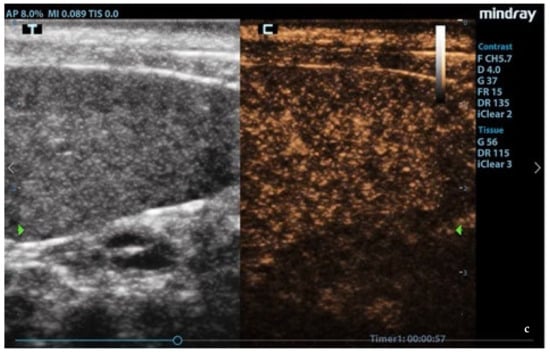

3.3. CEUS

In leishmaniotic dogs without splenic changes detectable from ultrasound examination and control dogs, CEUS exams showed the normal rapid enhancement of splenic arteries (10–13 s) and a heterogeneous phase of the enhancement of splenic tissue that became homogeneous at the end of wash-in with a slow decay (Figure 3).

Figure 3.

Normal spleen images acquired during CEUS (contrast-enhanced ultrasonography) exam. (a) Enhancement of the splenic arteries at 8 s after contrast injection; (b) beginning of heterogeneous phase of enhancement 10 s after contrast injection; (c) homogeneous enhancement at 60 s after contrast injection. F: probe’s frequencies; D: distance; G: gain; FR: frame rate; DR: dynamic range; AP: acoustic power; MI: mechanichal index; TIS: tissue imaging specific; M9: ultrasound system; T: tissue; C: contrast. Green arrows: focal points.

Enhancement in the moth-eaten parenchymas had a heterogeneous distribution pattern with hypoenhancement/no enhancement areas in both the wash-in and wash-out phases; in marbled spleens, enhancement intensity was weak and heterogeneous (Figure 4 and Figure 5).

Figure 4.

Moth-eaten spleen images acquired during CEUS exam. The heterogeneous enhancement of the parenchyma was persistently observed at: (a) 13 s, (b) 33 s, and (c) 60 s after contrast injection. F: probe’s frequencies; D: distance; G: gain; FR: frame rate; DR: dynamic range; AP: acoustic power; MI: mechanichal index; TIS: tissue imaging specific; M9: ultrasound system; T: tissue; C: contrast. Green arrows: focal points.

Figure 5.

CEUS images at the end of the wash-in phase in (a) moth-eaten, (b) marbled (heterogeneous enhancement), and (c) normal (homogeneous enhancement) spleens. F: probe’s frequencies; D: distance; G: gain; FR: frame rate; DR: dynamic range; AP: acoustic power; MI: mechanichal index; TIS: tissue imaging specific; M9: ultrasound system; T: tissue; C: contrast. Green arrows: focal points.

CPD examination and CEUS were used to study splenic microvascularization. After the inoculation of the contrast agent, normal splenic parenchyma showed the rapid enhancement of the small splenic arteries, a heterogeneous phase of enhancement that became homogeneous at the end of the wash-in phase, and a slow wash-out [39]. Though the contrast medium did not have a late tissue phase in the dog’s spleen, the slow decay of enhancement would have been related to the accumulation in the sinusoids network [40]. A CPD examination showed no flow signal from small hypoechoic areas in the moth-eaten pattern of the spleens. In moth-eaten spleens, CEUS was used for the first time and showed, through a persistence of diffuse inhomogeneity with areas of hypoenhancement or absence of enhancement, that the alterations found in the B-mode images also led to a modification of the vascular architecture throughout the organ. A similar heterogeneous appearance and a widespread hypoenhancement were also found in the marbled spleens. Spleen microvascular architecture changes emerged in L. infantum-positive dogs from an ultrastructural study independently of their antibody titers. A marked scarcity of the sinusoidal system sheet that surrounds the central artery/arteriole of the white pulp, a huge development of pulp venules and veins, and the presence of a development of reticular fibers were reported [13]. Interestingly, we evidenced that an abnormal pattern of enhancement was only in spleens with B-mode ultrasonography alterations, and we can only speculate about these results. This in vivo study of vascular architecture obtained with CEUS was, however, not able to highlight changes in the splenic vascular pattern in all infected dogs other than what was reported with ultrastructural evaluation [13]. The statistical analysis of the CEUS quantitative parameters, relating to the speed and volume of splenic blood flow, did not show statistically significant differences in the examined ROIs. This was probably due to the inhomogeneity of splenic enhancement in leishmaniotic subjects that was not quantitatively detectable through the pixel analysis of different areas, even when comparing relatively small ROIs, because of the widespread alteration of the splenic vascularity of parenchyma. Substantial evidence supports that the spleen plays a key role in the immunopathology of VBP infections [41,42]. Splenomegaly might be due to a multiplication of organisms within circulating mononuclear cells and mononuclear phagocytic tissues of spleen and lymph nodes. Splenomegaly is a result of reactive lymphoid hyperplasia and concurrent extramedullary hematopoiesis [43]. In canine babesiosis and ehrlichiosis, the most common splenic ultrasonographic findings have been a diffuse heterogeneous hypoechoic pattern and generalized splenomegaly [44,45]. CEUS exams were performed in the spleens of dogs with subclinical ehrlichiosis, and a higher velocity of blood flow (lower wash-in time, peak enhancement time, and wash-out time) compared to data from healthy dogs examined in previous studies was seen [45]. In our study, molecular investigations of blood samples and splenic aspirates showed them to be negative for R. conorii, B. canis, E. canis, A. phagocytophilum, A. platys, and C. burnetii, so we can consider it unlikely that the ultrasound changes of the spleen could be traced to other VBP coinfections with L. infantum.